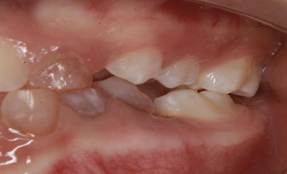

Figura 7. Relación molar derecha clase Figura

8. Relación molar izquierda clase III